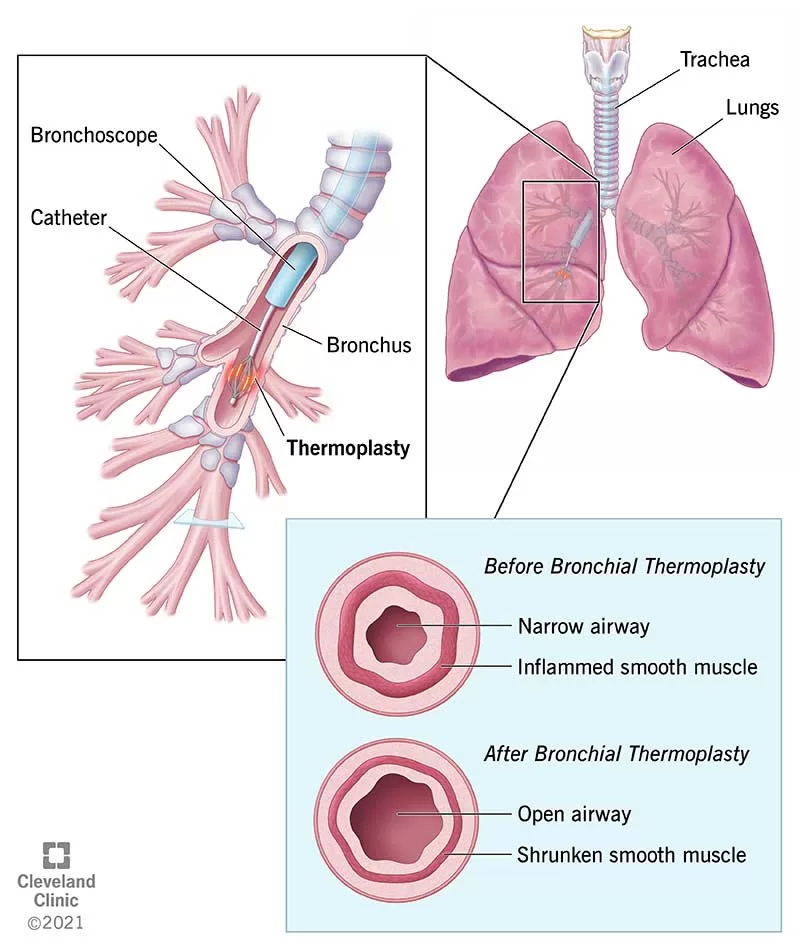

1. Asma

Asma adalah gangguan pada saluran pernapasan yang diakibatkan oleh kontraksi otot polos pada trakea dan mengakibatkan penderita sulit bernapas ditandai dengan kontraksi yang kaku dari bronkiolus.

Asma biasanya disebabkan oleh hipersensitivas bronkiolus terhadap benda-benda asing di udara. Penyebab penyakit ini juga dapat terjadi dikarenakan faktor psikis dan penyakit menurun.

4. Bronkitis

Bronkitis adalah penyakit karena peradangan pada bronkus. Penyebabnya bisa karena infeksi kuman, bakteri atau virus. Penyabab lainnya adalah asap rokok, debu, atau polutan udara.